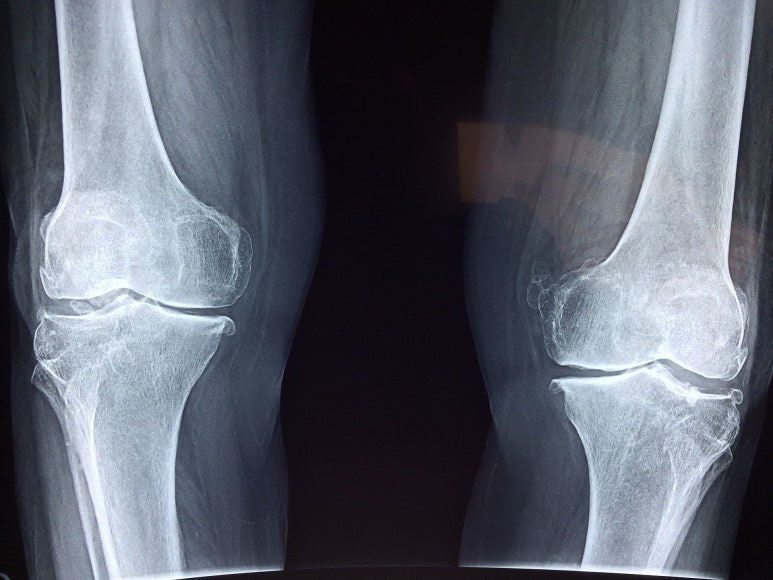

고관절 보다 약간 내측에 위치한 무릎은 체중의 지지가 많이 되는 내측 슬관절 부위로 퇴행성 변화가 진행되면서 다리 모양이 O자형으로 변형이 되고 관절 내 관절면의 연골 손상, 관절 주위 골극이 형성되어 인대와 근육의 약화가 동반하게 됩니다. 무릎 관절은 관절 내 압력이 높아지는 것과 동통은 직접적인 연관이 있는데 무릎 관절이 약 30도에서 40도 정도 구부러진 자세는 관절 내의 압력을 최소화하므로 퇴행성 관절염이 있는 사람들은 대부분 무릎이 구부정하게 구부리게 됩니다.

연골과 뼈가 서로 닿기 시작하면서 뼈 돌기가 자라난 상태로 앉거나 일어설 때 또는 자세를 바꿀 때, 무릎을 구부릴 때 통증을 호소하고 이유 없이 무릎이 붓는 현상이 나타나기도 합니다.

뼈와 뼈가 부딪혀 마찰이 생기고 연골이 전부 손상된 상태로 움직이지 않아도 극심한 무릎 통증이 발생하고 무릎의 모양이나 다리 모양의 변형이 오게 됩니다.